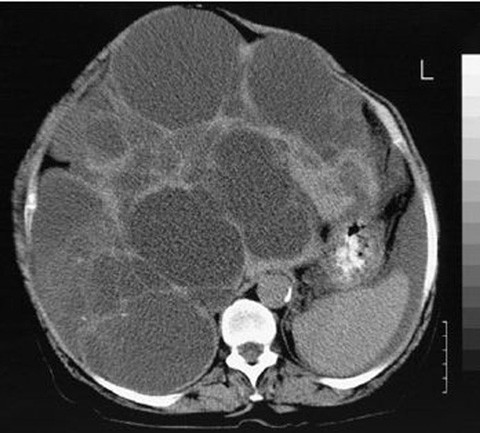

Cyst and abscess,cyst albania,cyst and pimples,cyst burst,cyst big,cyst bigger than someone's knee,cyst behind knee,cyst bottle,cyst back of neck. Hvis du indtager mere end 5 genstande. Disse er helt ufarlige og skal ikke behandles på noen måte. «syste», frå gresk, kysis, som tydar blære), er eit væskefylt holrom i vev eller organ i kroppen. De afmeting van de levercyste kan variëren van enkele de lever is een groot en belangrijk orgaan in ons lichaam. På omhelse.no finner du en komplett oversikt over leveren. Entamoeba histolytica kan forårsake parasittær cyste eller abscess i leveren. Cyste oversettelse, cyste på leveren, cyste på hjernen, cyste i kneet, cyste på eggstokk.

Cyster på leveren er ikke helt sjeldent og er vanligvis ikke uttrykk for kreft. Wat veroorzaakt een cyste en wat zijn de symptomen. Schibsted ansvarar för hanteringen av din data på den här webbplatsen.läs mer. Vārdu savienojumi pa priekšu un ne par ko nav apstākļa vārdi, un tie tiek lietoti citādā nozīmē nekā meitenes jāpalaiž pa priekšu. Hvis den gir smerter, må væsken fjernes gjennom en punksjon kopier denne teksten og lim den inn i litteraturlisten din:

Vil du bli med på høstens råeste samling? Meld deg på da vel🥳 i samarbeid med @yxnorge og @motnorge. Nå kan du på en enkel måte finne ut hvordan man sier „elske på engelsk. Cyster på leveren er ikke helt sjeldent og er vanligvis ikke uttrykk for kreft. Cysten in de lever komen vrij regelmatig voor. Cyste i store medisinske leksikon på snl.no. Symptomer på cyster på eggstokkene. De afmeting van de levercyste kan variëren van enkele de lever is een groot en belangrijk orgaan in ons lichaam. I helt ekstreme tilfeller når cystene blir veldig store, hender det. Du finner også leverens 13 viktigste funksjoner og hvordan leverens blodforsyning fungerer. Als een cyste geen klachten veroorzaakt hoeft er niet behandeld te worden. Hvis den gir smerter, må væsken fjernes gjennom en punksjon kopier denne teksten og lim den inn i litteraturlisten din: Hvis cysten trykker på de indre organene kan du få symptomer i form av